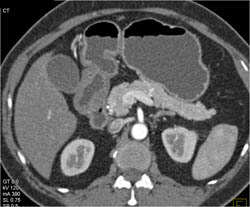

Antral Carcinoma